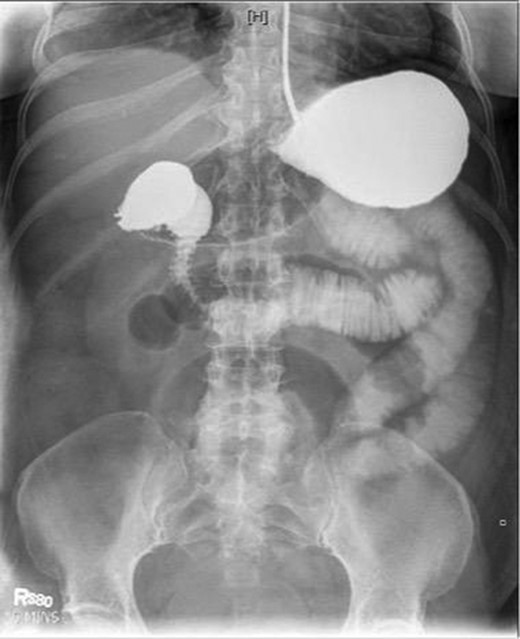

Laboratory studies were remarkable for leukocytosis, and an elevated lactate that improved with hydration (Fig. 1), while urinalysis was unremarkable. Abdominal CT scan obtained at this time demonstrated a partial SBO in the mid-small bowel as well as inflammation and thickening of the duodenum. A small bowel series was ordered, and showed high grade SBO (Figs 2–5).

Fluoroscopic barium study demonstrating oral contrast agent progression through the small bowel at 5 min after ingestion.